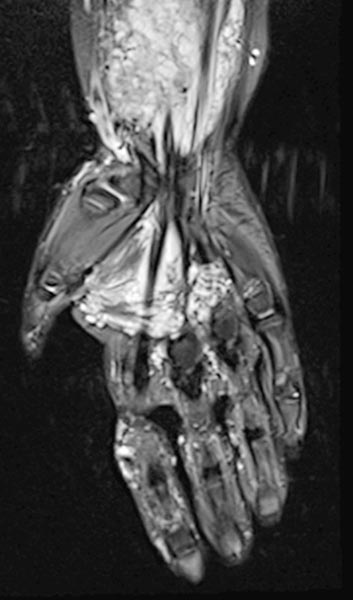

The venous malformation shows deep extension in the deep flexor tendons of the hand and forearm on T2-weighted, fat-suppressed MRI.

On the distal right forearm in the area of the main extension of the swelling, the bulk of the venous malformation is seen predominantly in the flexor muscles. Severely hyperintense MRI signal in T2w fat saturation. The entire flexor muscles are intermingled.